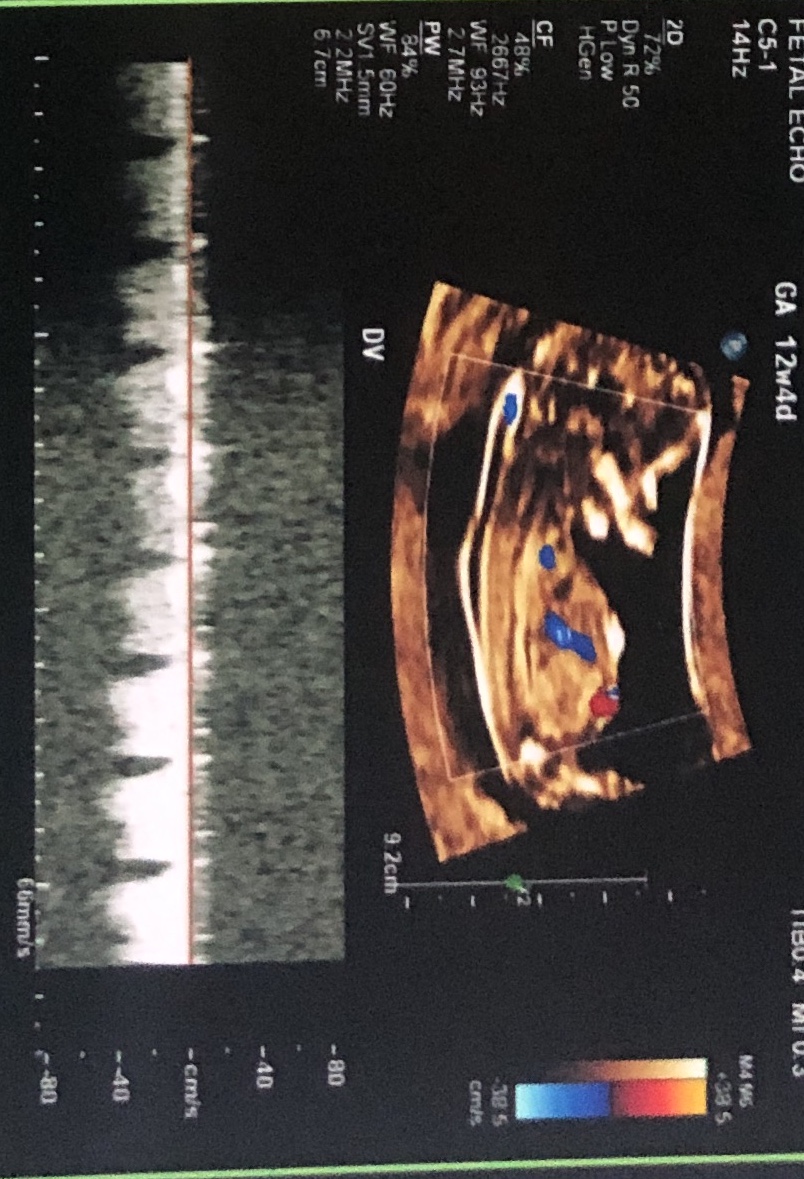

Little anxious to find our little one’s gender. Attached are ultrasound images at 12+4 days (age as per CRL dating)Attachment 42397Attachment 42398Attachment 42397Attachment 42398